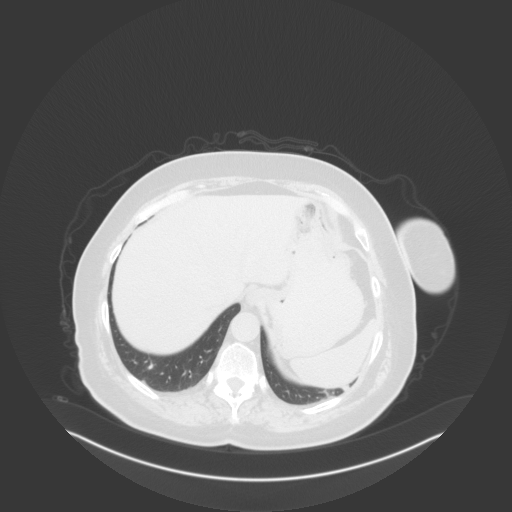

Original NATIVE CT scan (input)

No window - Raw intensity values

Lung window (WL -600, WW 1500 β†’ Low βˆ’1350, High +150)

Mediastinum window (WL 40, WW 400 β†’ Low βˆ’160, High +240)